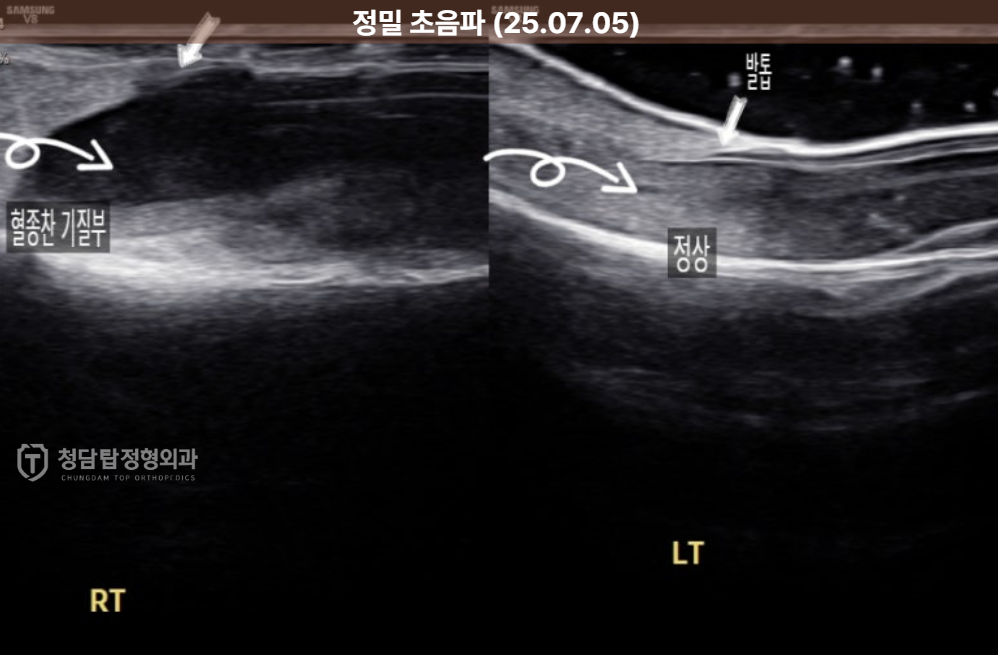

정확한 원인 규명을 위해 추가적으로 정밀 초음파 검사를 시행해보니,

아니나 다를까 발톱 판 아래에 피가 고여있는게 보였습니다.

건강한 반대쪽 발가락과 비교하니 차이가 확연했습니다.

이걸 의학용어로는 '조갑하 혈종'이라고 부릅니다.